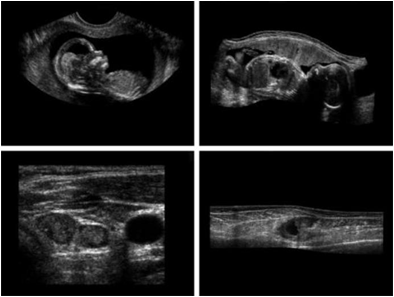

Other imaging modalities

a)아기1 b)아기2 c)갑상선 d)손상된근육